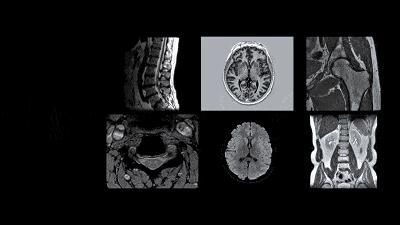

超聲、CT、X線、MRI……影像檢查種類繁多,有時還會交叉,而不同部位的疾病在檢查確診時其實都有最優選擇。

◉CT檢查:腦部疾病首選

CT檢查可發現大部分腦部疾病,包括先天性腦發育顱內異常、腦腫瘤、腦血管病、顱腦外傷等。

但對於某些腦變性疾病,垂體微腺瘤、小轉移瘤等較小病變,以及椎管內(包括脊髓)的各類疾病,CT的價值較爲有限。

MRI(磁共振成像):CT的補充

MRI可作爲急性腦梗死、腦轉移瘤等的首選檢查,是CT檢查的重要補充;CT檢查不出的椎管內疾病,MRI是首選檢查技術。

MRI:優於CT檢查

由於軟組織中的肌肉、血管、神經和關節囊等組織間密度差別不大,X光片無法分辨,而MRI明顯優於X光片、CT。因此,懷疑腫瘤、壞死、出血和水腫等情況時,優選MRI。